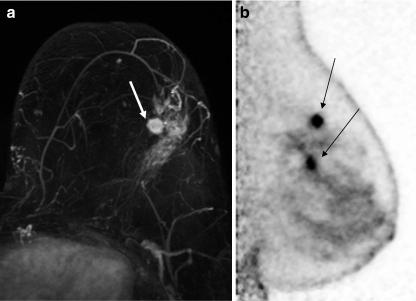

The objective of this study was to compare the performance characteristics of (18)F-fluorodeoxyglucose (FDG) positron emission mammography (PEM) with breast magnetic resonance imaging (MRI) as a presurgical imaging and planning option for index and ipsilateral lesions in patients with newly diagnosed, biopsy-proven breast cancer.

Two hundred and eight women >25 years of age (median age = 59.7 ± 14.1 years) with biopsy-proven primary breast cancer enrolled in this prospective, single-site study. MRI, PEM, and whole-body positron emission tomography (WBPET) were conducted on each patient within 7 business days. PEM and WBPET images were acquired on the same day after intravenous administration of 370 MBq of FDG (median = 432.9 MBq). PEM and MRI images were blindly evaluated, compared with final surgical histopathology, and the sensitivity determined. Substudy analysis compared the sensitivity of PEM versus MRI in patients with different menopausal status, breast density, and use of hormone replacement therapy (HRT) as well as determination of performance characteristics for additional ipsilateral lesion detection.

Two hundred and eight patients enrolled in the study of which 87% (182/208) were analyzable. Of these analyzable patients, 26.4% (48/182), 7.1% (13/182), and 64.2% (120/182) were pre-, peri-, and postmenopausal, respectively, and 48.4% (88/182) had extremely or heterogeneously dense breast tissue, while 33.5% (61/182) had a history of HRT use. Ninety-two percent (167/182) underwent core biopsy for index lesion diagnosis. Invasive cancer was found in 77.5% (141/182), while ductal carcinoma in situ (DCIS) and/or Paget's disease were found in 22.5% (41/182) of patients. Both PEM and MRI had index lesion depiction sensitivity of 92.8% and both were significantly better than WBPET (67.9%, p < 0.001, McNemar's test). For index lesions, PEM and MRI had equivalent sensitivity of various tumors, categorized by tumor stage as well as similar invasive tumor size predictions with Spearman's correlation coefficient of 0.61 for both PEM and MRI compared to surgical pathology. Menopausal status, breast density, and HRT did not influence the sensitivity of PEM or MRI. For 67 additional unsuspected ipsilateral lesions or multifocal lesions, PEM had sensitivity of 85% (34/40) and specificity of 74%, (20/27) compared to MRI's sensitivity of 98% (39/40) and specificity of 48% (13/27) [p = 0.074, for sensitivity; p = 0.096 for specificity]

PEM is a good alternative to MRI as a presurgical breast imaging option and its performance characteristics are not affected by patient menopausal/hormonal status or breast density.